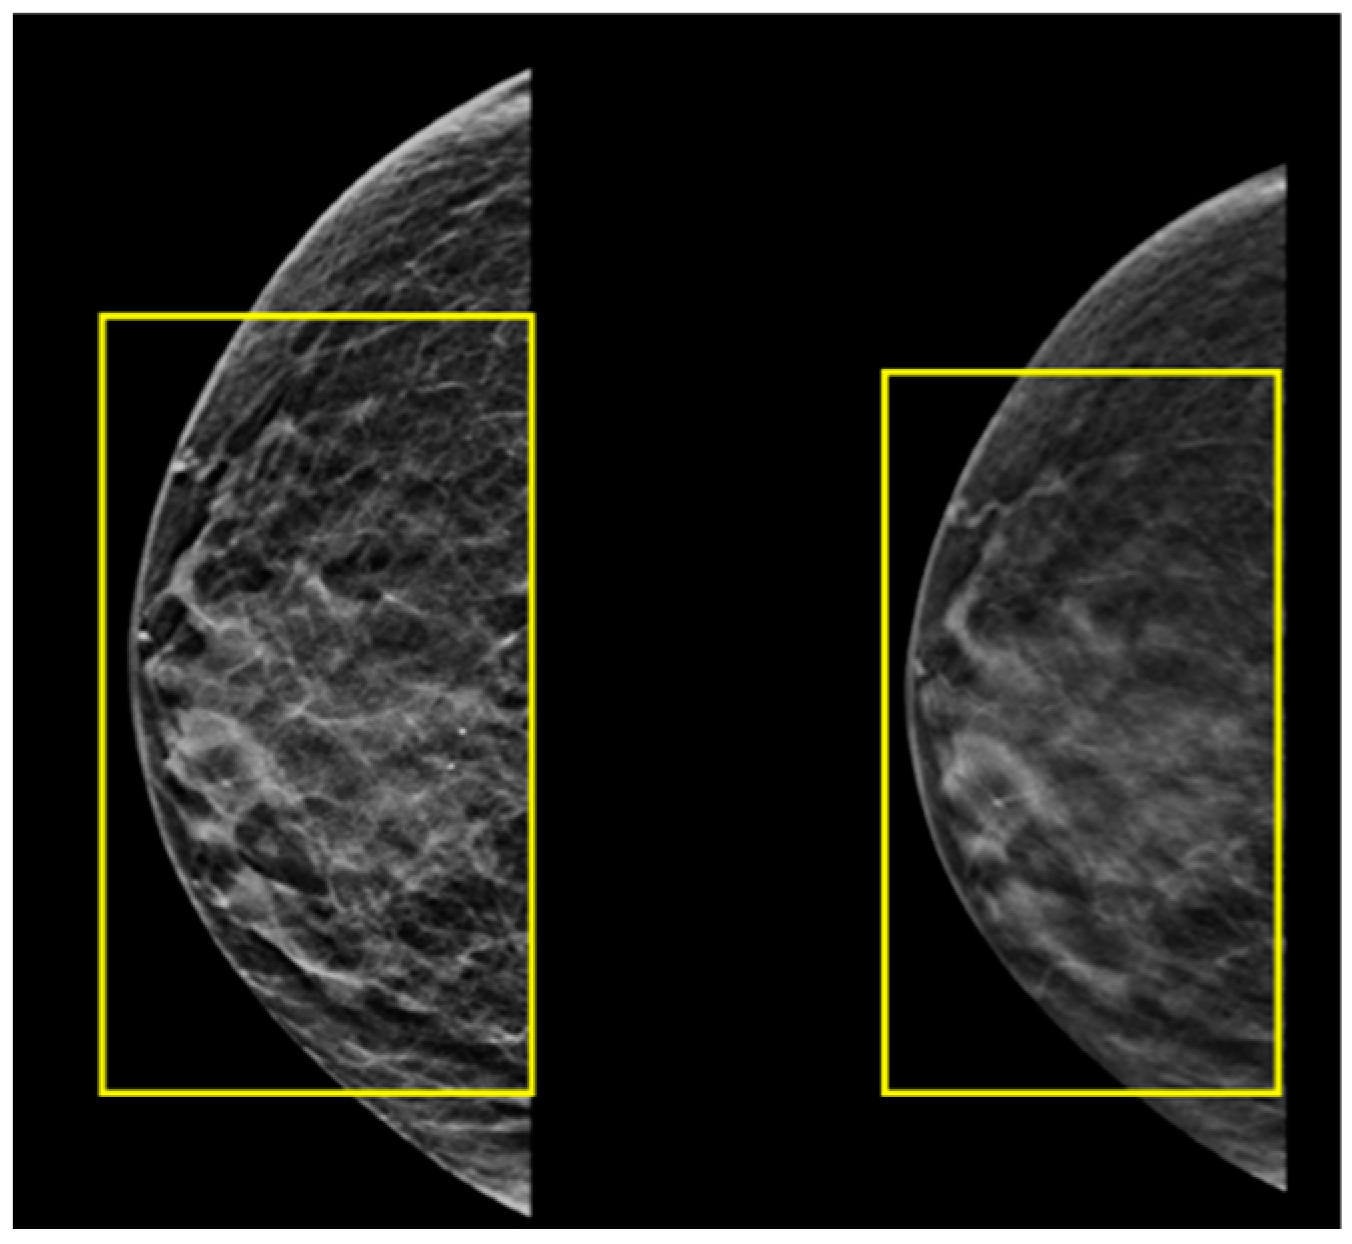

2.5. A Male with Breast Cancer Metastasized to the Left Kidney

| 5 | 73 | M | Breast Carcinoma | Left Kidney | CT Histopathology | Resection Tamoxifen |